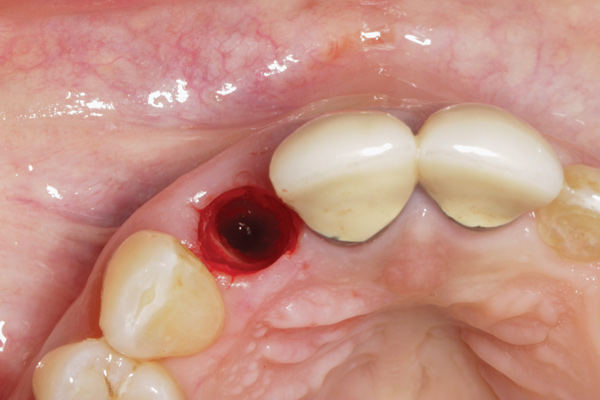

Fig 1. Clinical photograph showing significant issues related to implant midfacial mucosal recession and loss of interdental papillae. This is attributed to incorrect implant positioning (too buccal and too deep); several corrective surgeries resulted in interproximal bone loss, then loss of interdental papillae.

Figure 1